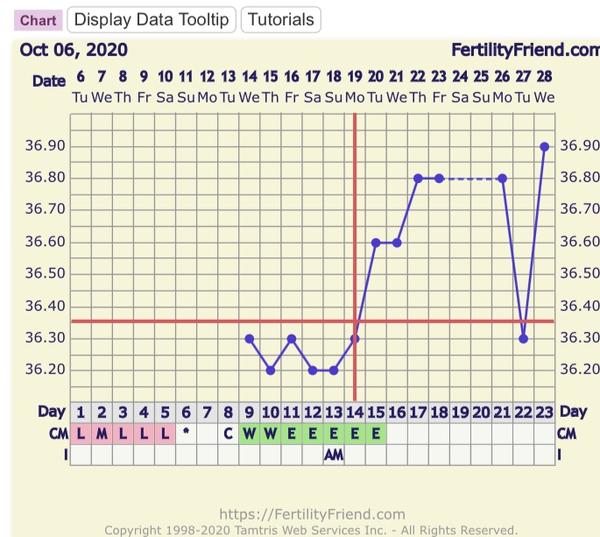

Grafy bazálnej teploty

Baby, nová téma o grafoch BT, ovulačných testoch, tehotenských testoch a hľadaní duchov je tu 🙂

Ak meriate bazálnu teplotu a zapisujete si hodnoty do grafov, ste na správnom mieste. Poradíme, pomôžeme, podporíme.

Grafy si môžete vytvárať na nasledovných stránkach:

www.fertilityfriend.com

www.womenzone.cz

www.wunschkinder.net

Všetko o meraní BT a jednotlivých programoch na vytváranie grafov nájdete tu: http://merenibt.xf.cz/index2.html